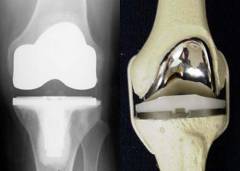

Хирургическое лечение необходимо при разрушении суставных поверхностей и образовании массивных остеофитов, часто с заменой сустава эндопротезом.

Эндопротезирование сустава

| Показания | Методика | Цель операции | Длительность реабилитации |

| Отсутствие эффекта от медикаментозного лечения, прогрессирующее разрушение хрящевой и костной ткани. | Операция под общим наркозом, удаление разрушенной ткани и установка эндопротеза. | Замена пораженного сустава. | Зависит от прооперированного сустава, выписка через 10–14 дней после операции. |

Хирургическое вмешательство необходимо при полном разрушении суставных поверхностей и образовании крупных остеофитов. В таких случаях проводят замену сустава на эндопротез (протез, установленный внутри организма). Материалы протеза обеспечивают долговечность и износостойкость. Обычно он восстанавливает полный объем движений и устраняет боль.

| Отсутствие эффекта от консервативного лечения, прогрессирующее разрушение хрящевой и костной ткани, наличие крупных остеофитов. | Операция проводится под общим наркозом. В зависимости от сустава, продолжительность и объем вмешательства могут различаться. Хирург получает доступ к суставу через разрез, удаляет поврежденные хрящ и часть костной ткани, устанавливает эндопротез. Элементы протеза фиксируются к кости с помощью шурупов или цемента. В конце операции может быть установлен дренаж для отведения крови и воспалительного экссудата. | Удаление поврежденного сустава и его замена на эндопротез. | Реабилитация зависит от прооперированного сустава. При эндопротезировании коленного сустава выписка возможна на 10-14 день. В течение 6 недель рекомендуется ограничить физическую нагрузку на сустав (использовать трость). Реабилитация после операции на тазобедренном суставе занимает около 8 недель, на плечевом — 5 недель. |